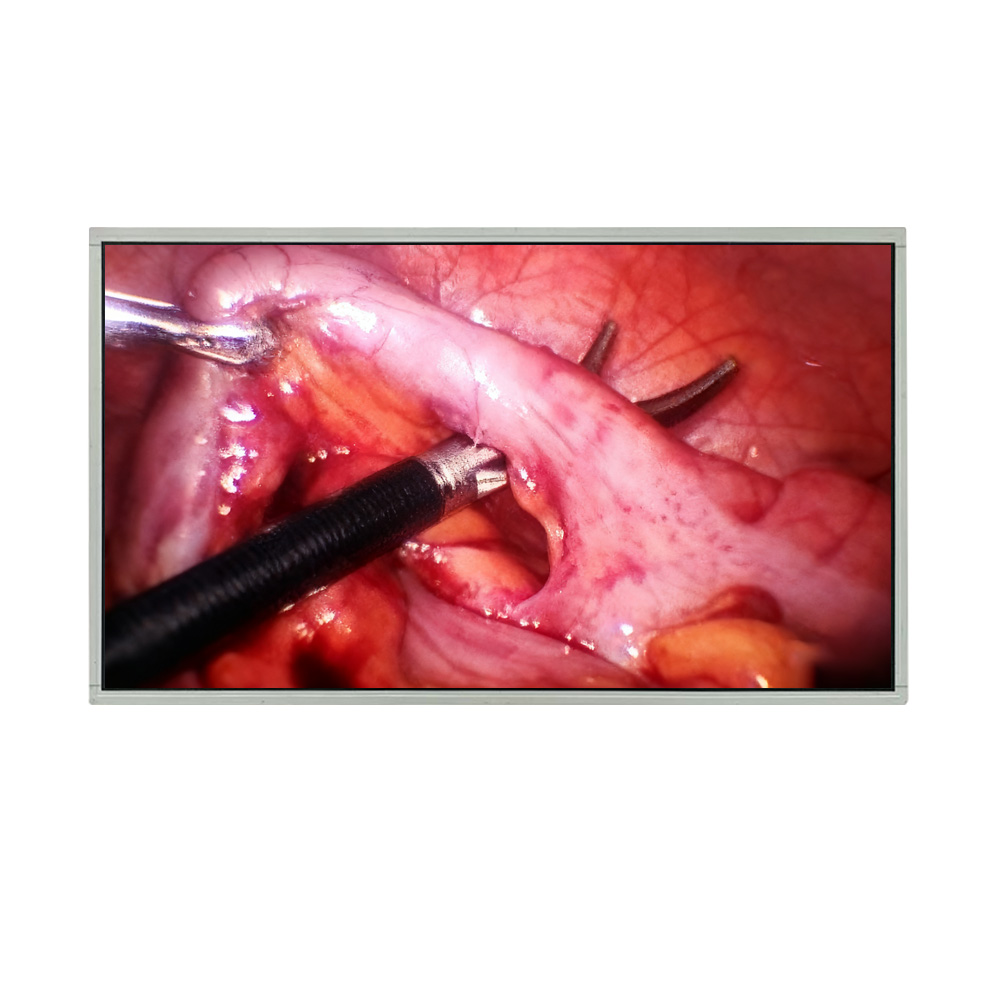

Medical Monitors and Displays: Innovations Shaping Modern Healthcare

Explore the latest in medical monitors and displays. Discover why the Precision 32-Inch 4K LCD Module (DBT320DZN51E050B) delivers unmatched clarity, reliability, and integration for operating rooms, radiology, and PACS systems.

Can I Find Active Matrix LCDs Suitable for Medical or Healthcare Use?

Active matrix LCDs are the gold standard for medical and healthcare applications. Discover the Precision 32-Inch 4K LCD Module (DBT320DZN51E050B), a high-resolution medical display optimized for surgical monitors, radiology workstations, and diagnostic equipment.